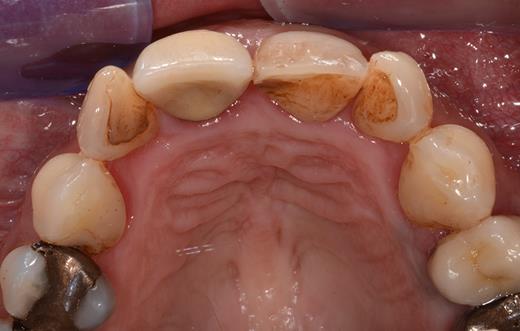

Clinical examination revealed two small mucosal openings on either side of the incisive papilla, which could be probed partially (Fig. 1). Palpation of this area was painful. Two gutta-percha points were inserted into the two openings (Fig. 2). The cone beam computed tomography (CT) confirmed two patent NDPs with oronasal communication (Fig. 3).

Preoperative clinical situation: occlusal view of the maxillary arch presenting two small depressions of the mucosa on either side of the incisive papilla (blue arrows).